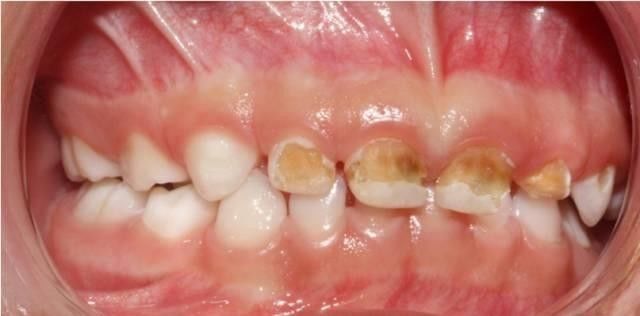

奶瓶龋最初在上颌乳切牙的唇面龈缘处出现白垩色斑点或带状脱矿,而后逐渐向下向旁边蔓延,侵蚀邻近的牙面形成环状龋,呈棕褐色,并最终发生牙冠折断,仅留下残根。

让孩子抱着奶瓶,就去上床睡觉,几周,几个月下来就会这样,妈咪再不重视也不去医院治疗。。。

过了差不多3个月吧,这天,慧慧发现孩子的牙齿用手一碰就会坠落一些物质,刚开始坠落的仍是一些白色物质,后来直接掉的物质类似于矿物质,孩子张嘴一看,慧慧发现现已没有几颗好牙了。慧慧就带孩子去医院查看,医师说孩子这是患了奶瓶龋。这是由于孩子长期含奶嘴的原因。